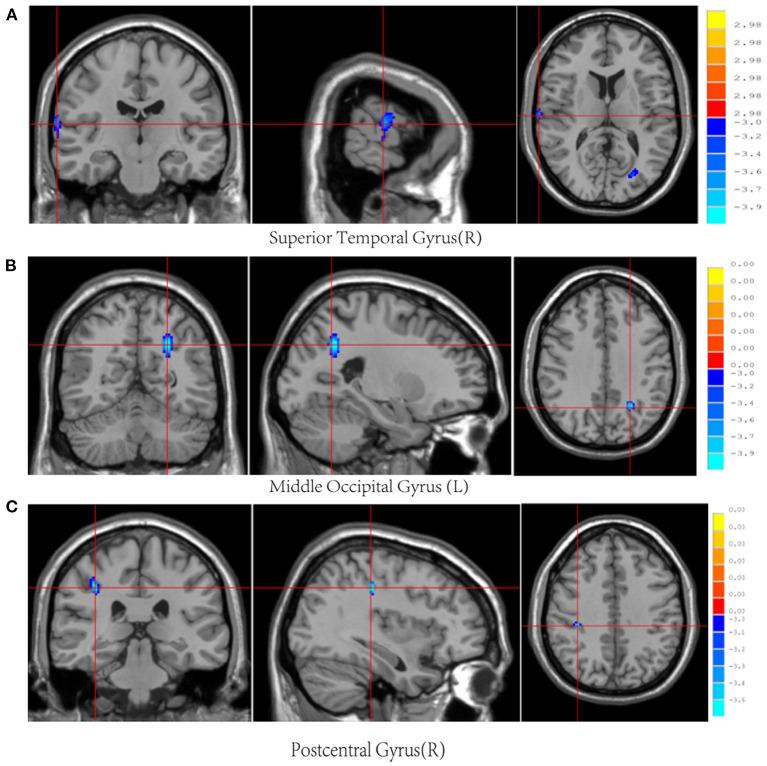

This study aimed to investigate sex differences in cerebral blood flow (CBF) and serum inflammatory cytokines, as well as their correlations in patients with acute-stage mild traumatic brain injury (mTBI). Forty-one patients with mTBI and 23 matched healthy controls underwent 3D-pseudo-continuous arterial spin labeling imaging on 3T magnetic resonance imaging. The patients underwent cognitive evaluations and measurement of a panel of ten serum cytokines: interleukin (IL)-1I, IL-4, IL-6, IL-8, IL-10, IL-12, C-C motif chemokine ligand 2, interferon-gamma, nerve growth factor-beta (β-NGF), and tumor necrosis factor-alpha (TNF-α). Spearman rank correlation analysis was performed to evaluate the relationship between inflammation levels and CBF. We found that both male and female patients showed increased IL-1L and IL-6 levels. Female patients also demonstrated overexpression of IL-8 and low expression of IL-4. As for CBF levels, three brain regions [the right superior frontal gyrus (SFG_R), left putamen, and right precuneus] increased in male patients while three brain regions [the right superior temporal gyrus (STG_R), left middle occipital gyrus, and right postcentral (PoCG_R)] decreased in female patients. Furthermore, the STG_R in female controls was positively correlated with β-NGF while the right PoCG_R in female patients was negatively correlated with IL-8. In addition, compared with male patients, female patients showed decreased CBF in the right pallidum, which was negatively correlated with IL-8. These findings revealed abnormal expression of serum inflammatory cytokines and CBF levels post-mTBI. Females may be more sensitive to inflammatory and CBF changes and thus more likely to get cognitive impairment. This may suggest the need to pay closer attention to the female mTBI group.

本研究旨在探讨急性轻度创伤性脑损伤(mTBI)患者脑血流量(CBF)和血清炎症细胞因子的性别差异及其相关性。41例mTBI患者和23例匹配的健康对照者接受了3T磁共振成像的三维伪连续动脉自旋标记成像。患者接受了认知评估,并检测了一组十种血清细胞因子:白细胞介素(IL)-1I、IL-4、IL-6、IL-8、IL-10、IL-12、C-C基序趋化因子配体2、干扰素-γ、神经生长因子-β(β-NGF)和肿瘤坏死因子-α(TNF-α)。采用Spearman等级相关分析评估炎症水平与CBF之间的关系。我们发现,男性和女性患者的IL-1L和IL-6水平均升高。女性患者还表现出IL-8的过表达和IL-4的低表达。至于CBF水平,男性患者的三个脑区[右侧额上回(SFG_R)、左侧壳核和右侧楔前叶]增加,而女性患者的三个脑区[右侧颞上回(STG_R)、左侧枕中回和右侧中央后回(PoCG_R)]减少。此外,女性对照组的STG_R与β-NGF呈正相关,而女性患者的右侧PoCG_R与IL-8呈负相关。此外,与男性患者相比,女性患者右侧苍白球的CBF降低,这与IL-8呈负相关。这些发现揭示了mTBI后血清炎症细胞因子表达和CBF水平异常。女性可能对炎症和CBF变化更敏感,因此更易发生认知障碍。这可能提示需要更加关注女性mTBI组。